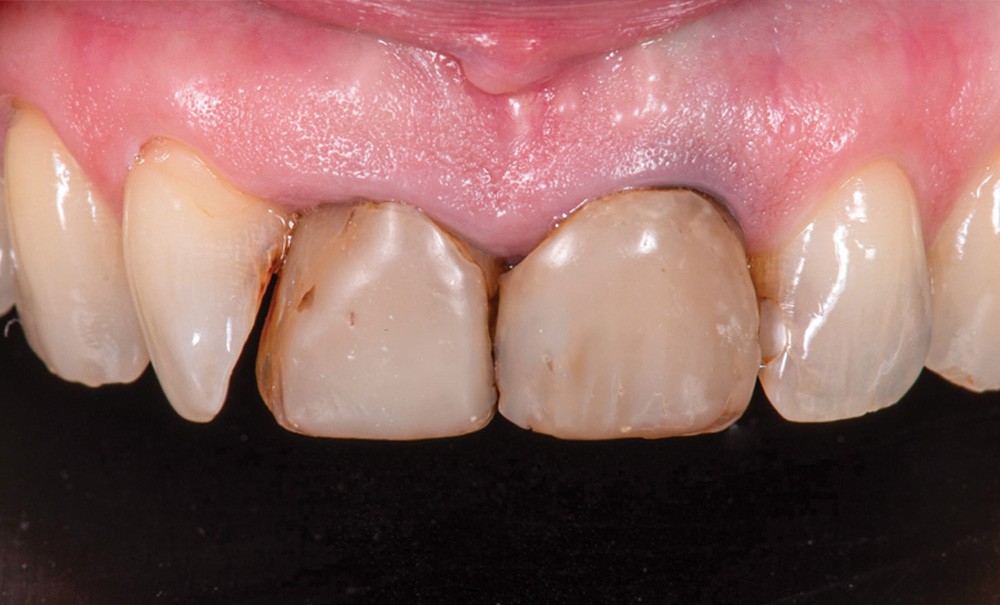

- provisoires de première génération sur 11 et 21, empreintes numériques simples des préparations périphériques dans le but d’élaborer des modèles de diagnostic de laboratoire imprimés (fig. 3 et 4) ;

Le but de cet article est de mettre en avant les matériaux utilisés dans une réhabilitation esthétique partielle composée de deux couronnes périphériques sur 11 et 21 et d’une facette vestibulaire sur 12.